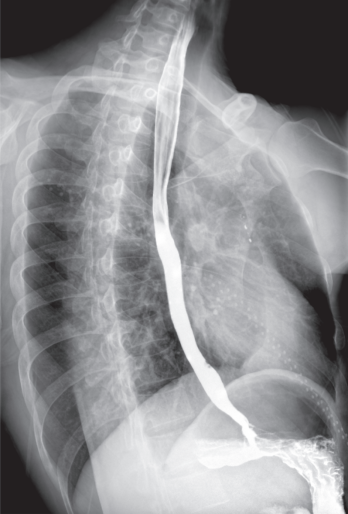

该系统核心优势在于整合动态透视与三维成像技术。在脊柱全长摄影、双下肢负重位检查中,可一次性获取颈椎至骶尾椎的高清全景影像,避免传统分段拍摄的拼接误差,为脊柱侧弯、关节畸形等疾病的力线测量和手术规划提供精准数据。其动态功能成像模块能实时捕捉关节运动状态下的解剖结构变化,清晰显示膝关节屈伸、肩关节活动时的软组织动态,显著提高韧带损伤、关节不稳等隐匿性病变的检出率。